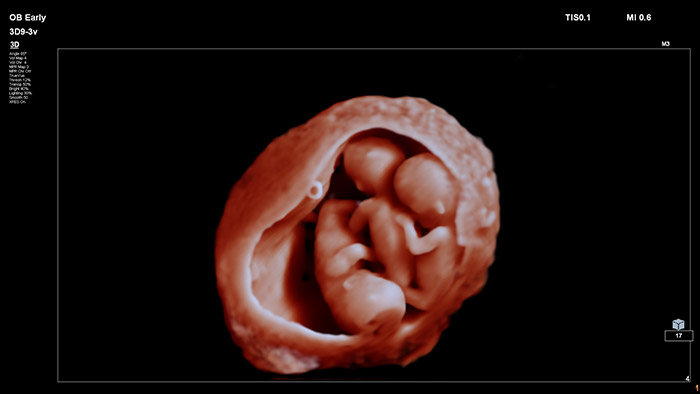

在该视频中,Michael Ruma 博士展示了飞利浦 V9-2 三维超声探头。V9-2 是飞利浦超声首个用于妇产科检查的纯净波三维机械探头,提供了卓越的图像质量和先进的人体工程学设计。V9-2 探头尤其适用于孕早期、孕中期和孕晚期产科检查的二维、三维、四维成像。

新型 V9-2 探头搭配 EPIQ Elite 卓越超声诊断系统,提供优质的妇产科成像:

先进的产科可视化工具实现逼真的胎儿渲染。